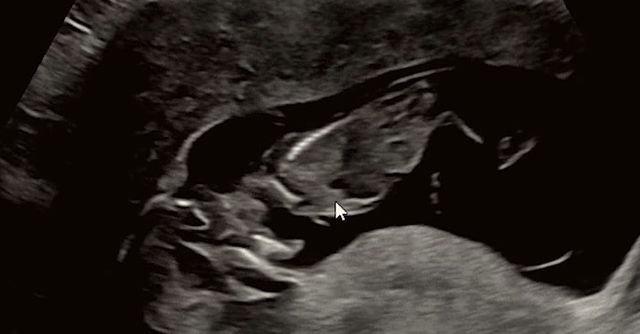

임신 12주차였을 때 초음파 사진 / 유튜브 '변비부부'